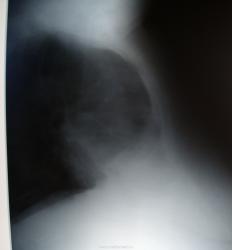

Пол пациента: Женский пол Тип патологии: Инфекция Область исследования: Грудная клетка и верхние дыхательные пути Методы исследования: Rg В приёмное отделение поступила пожилая женщина, которая поведала доктору о том. что её около недели беспокоит кашель и незначительное повышение температуры до субфебрильных цифр. Был сделан снимок в двух проекциях. https://radiomed.ru/sites/default/files/styles/case_slider_image/public/user/712/sl272945.jpg?itok=wtGPiRaB ID:5790 Ср, 25/08/2010 - 00:19 #1 Сан Саныч1 Не на сайте Был на сайте: 11 месяцев 2 недели назад Зарегистрирован: 07.06.2010 - 21:17 Публикации: 2114 Полечить пневмонию, если нет возм-ти сделать КТ, а потом с чистой совестью в ОД. Хочешь сделать что-то нормально - сделай это сам! Ср, 25/08/2010 - 15:18 #2 Катенёв Валенти... Не на сайте Был на сайте: 7 лет 2 недели назад Зарегистрирован: 22.03.2008 - 22:15 Публикации: 54876 Справа паракостально, по всей видимости, незначительное осумкование Приложения:

Справа паракостально, по всей видимости, незначительное осумкование